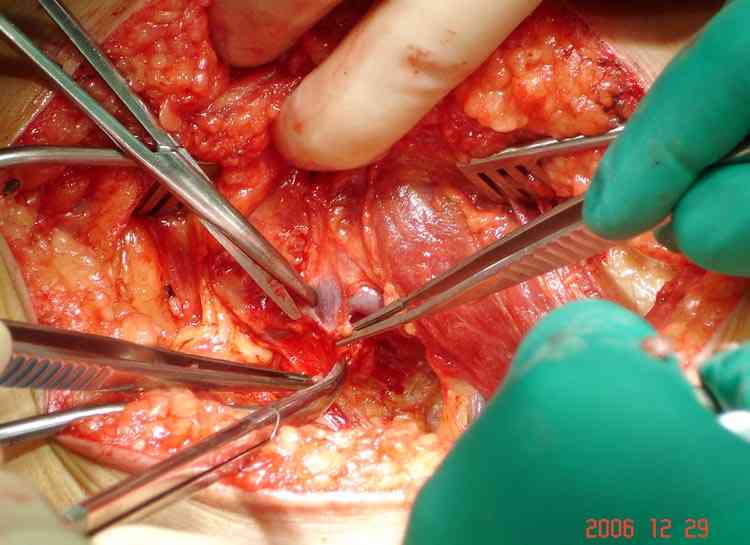

Ангиография подтвердила васкулярную аневризму в

результате давления экзостозом. Совместно с сосудистым хирургом была проведена плоскостная резекция с дальнейщим восстановлением сосуда венозным графтом.